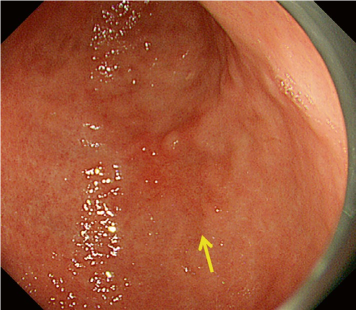

The working group members carried out a systematic review of the English literature to determine widely accepted diagnostic systems. Consequently, the best-accepted diagnostic system was proven to be the VS classification system. Based on this system, MESDA-G was constructed using an evidence-based approach (. Figs. 3, 4, 5, and 6) [2]. First, lesions suspicious for EGC should be detected by careful inspection using conventional white-light endoscopy. Subsequently, magnified observations should be performed. Owing to the high sensitivity of the demarcation line [8], if it is absent, the suspicious lesion is diagnosed as noncancerous (. Fig. 4a, b). However, if the demarcation line is present, further assessment is required to determine the presence of an irregular MV or MS pattern. If an irregular MV and/or MS pattern is detected, the suspicious lesion is diagnosed as cancerous (. Fig. 6a, b) [1, 5, 6, 8]. If both the irregular MV and MS patterns are absent, the tumor is diagnosed as noncancerous (. Fig. 5a, b) [1, 5, 6, 8].